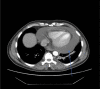

Abstract: Pembrolizumab is an immune checkpoint inhibitor used in various types of cancers. Pericardial tamponade is a rare side effect reported in only very few case reports. Early recognition and therapeutic intervention is vital in all cases. We report a case of a 54-year-old male with Stage 3 lung adenocarcinoma who developed cardiac tamponade secondary to pembrolizumab and subsequently required pericardial window.